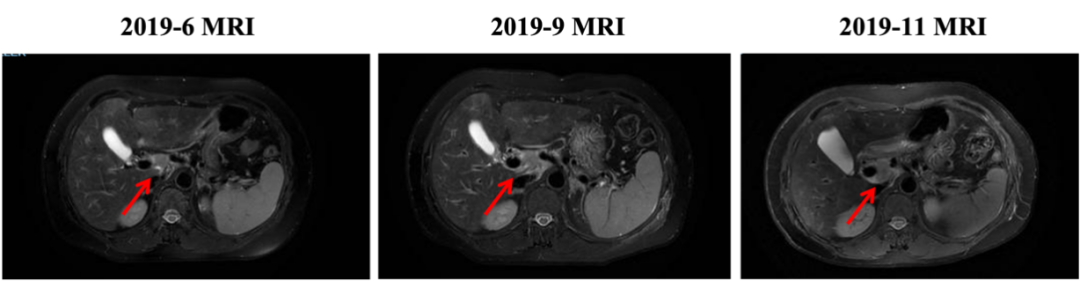

入组MO28231临床试验,于2016-12-1开始行T-DM1治疗,具体:T-DM1 3.6mg/kg 237.6mg d1,Q21d。最佳评效PR。肝门区淋巴结自2019-6出现,逐渐增大,2019-11增大至29*22mm,考虑转移,判定为新发病灶PD出组,共治疗48周期,PD时间为2019-6,PFS为30月。不良反应:胆红素升高1级,血小板下降1级,疲劳1级,鼻出血1-2级,关节僵硬1级,手足麻木1级。

图4. 三线治疗